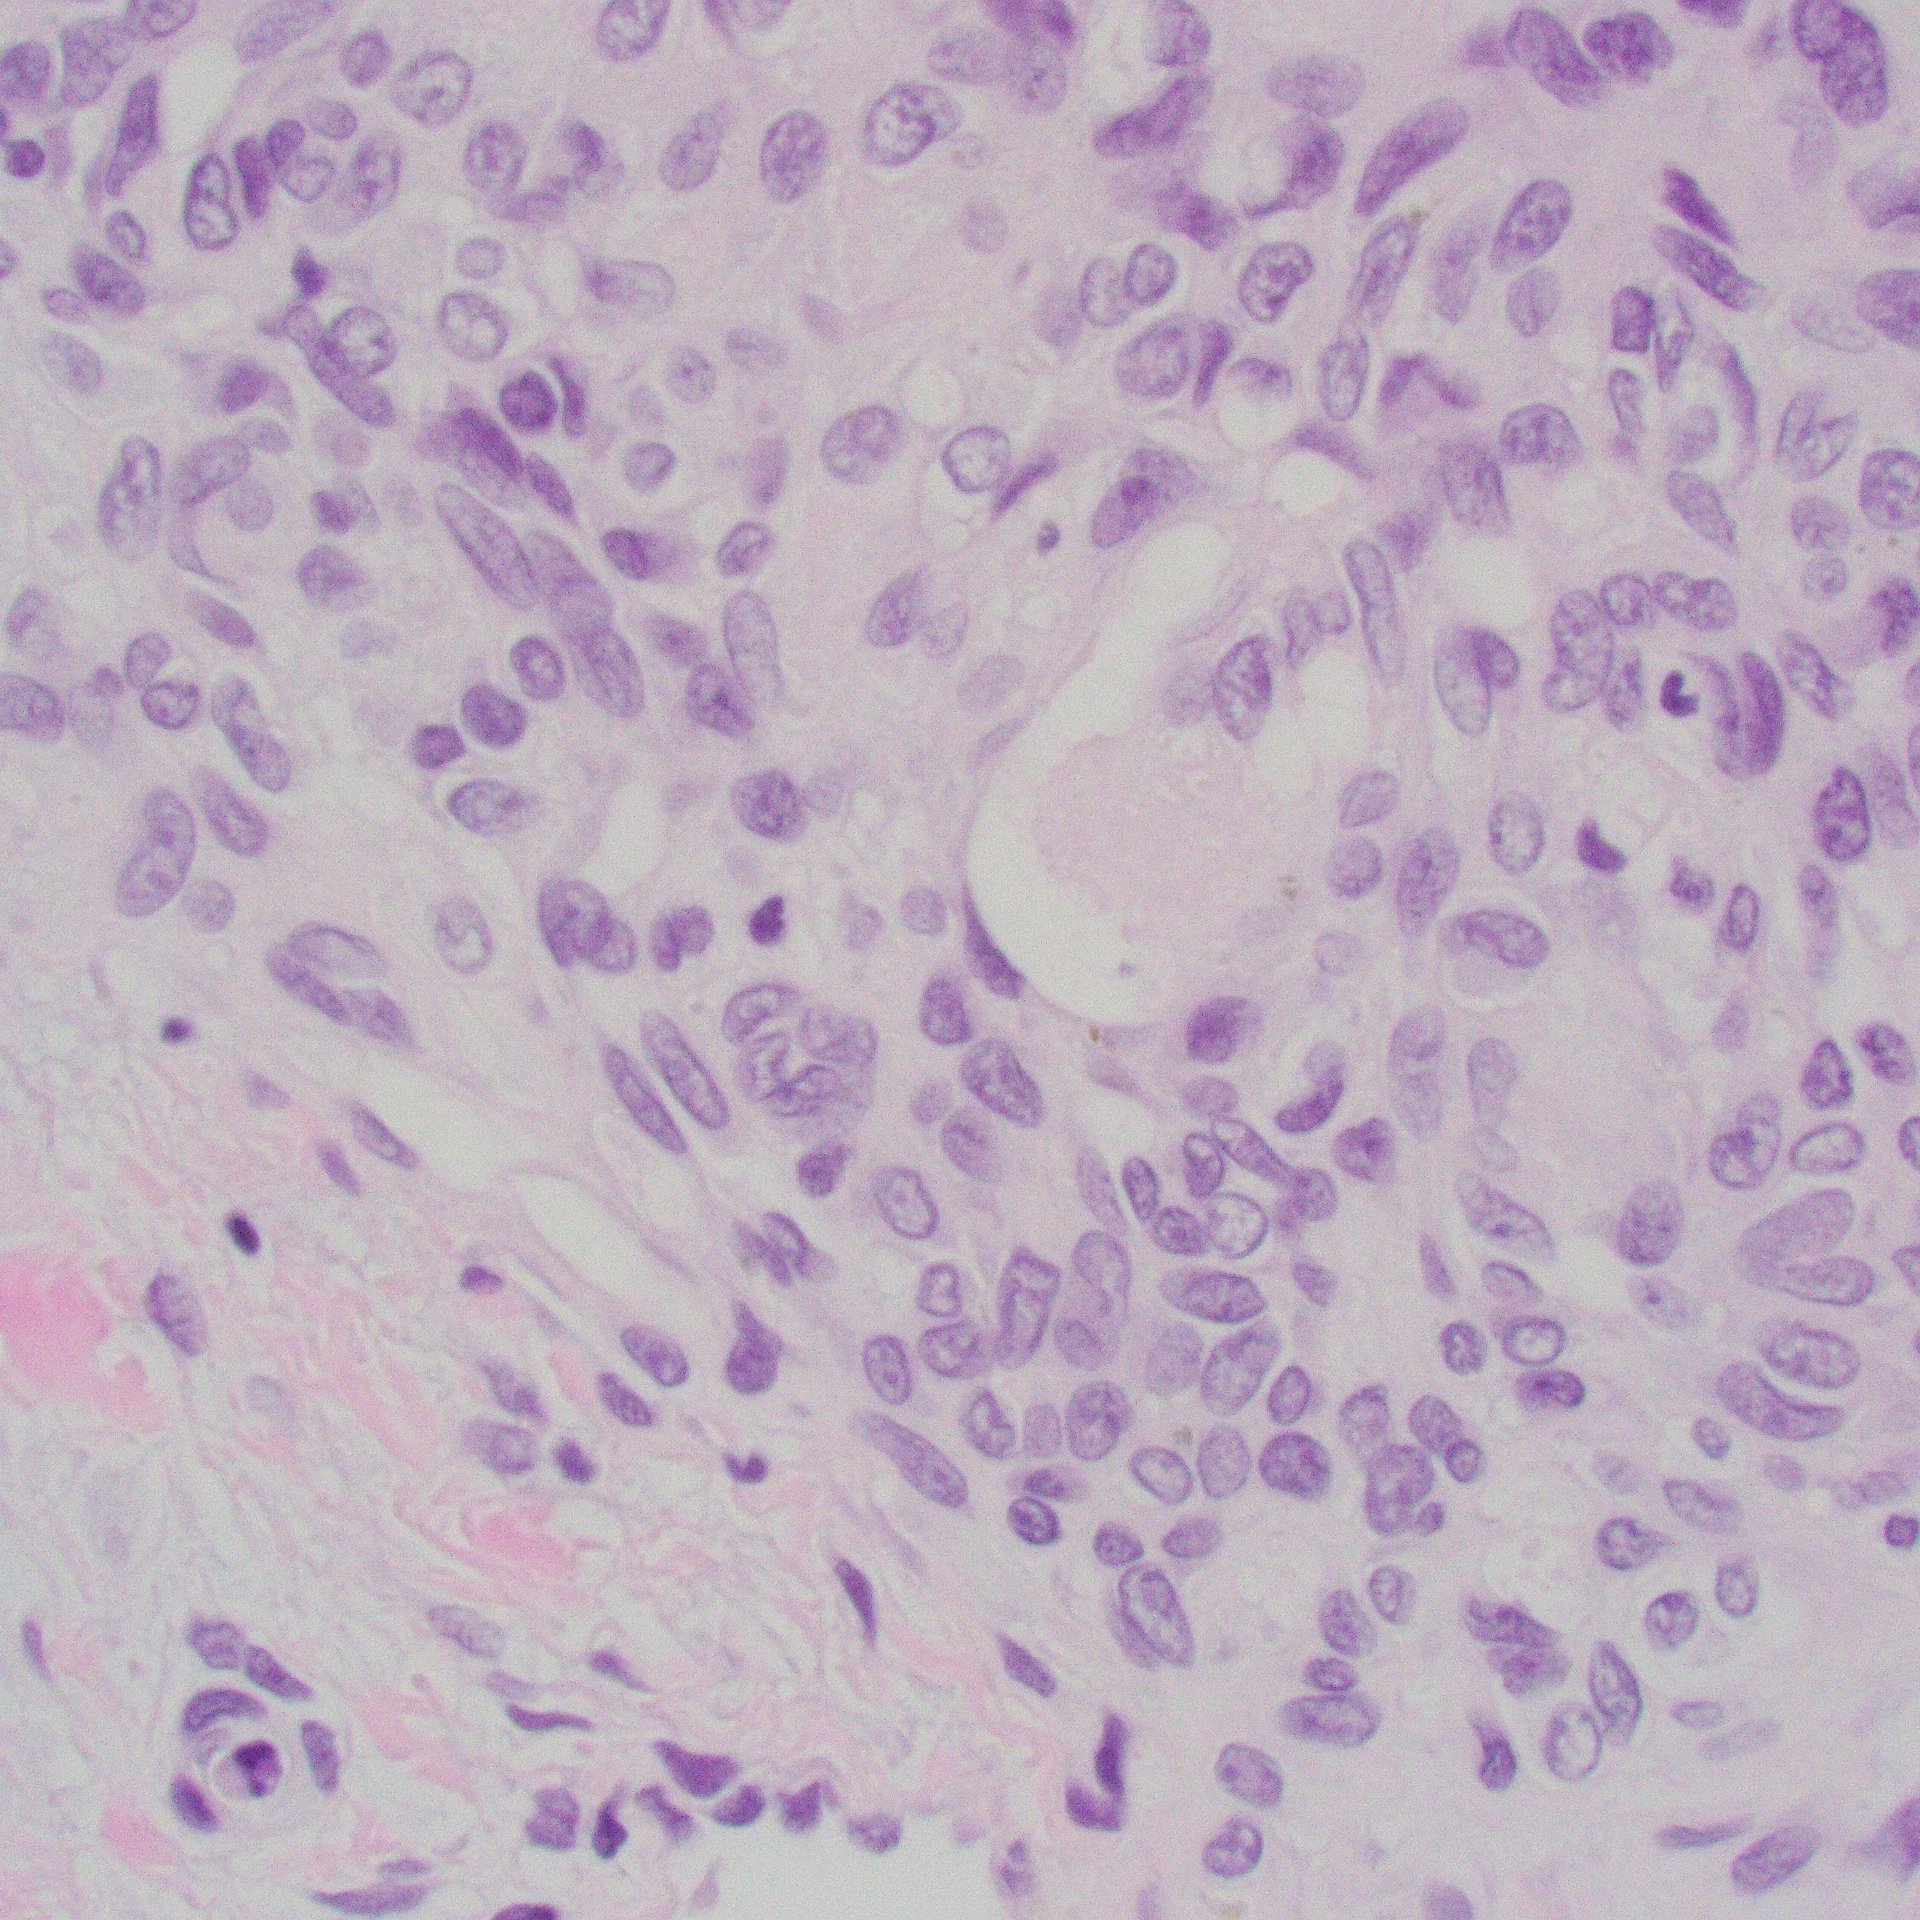

Case 4: Small round cell tumor

Images

IHC: CD99 (diffuse membranous), WT1 (patchy)

Diagnosis

CIC-rearranged sarcoma (CIC-DUX4 sarcoma)

- Monotonous, mild nuclear pleomorphism

- “Atypical” EwS

- Chromatin pattern more coarse and more prominent nucleoli than Ewing sarcoma (EwS)

- Site:

- Deep soft tissue of the limbs or trunk > head and neck, retroperitoneum, and pelvis; 10% arise in viscera (kidney, gastrointestinal tract, and brain)

- CIC::DUX4 fusion

- Present in 95% of cases

- Either a t(4;19)(q35;q13) or a t(10;19)(q26;q13)

- Less common partner genes: FOXO4, LEUTX, NUTM1, and NUTM2A

- IHC:

- Positive for CD99 (diffuse or patchy, membranous and/or cytoplasmic)

- WT-1 (nuclear with or without cytoplasmic in up to 95% of cases)

- ETV4

- Aggressive tumours, with frequent metastases and a poor outcome; EwS therapy less effective